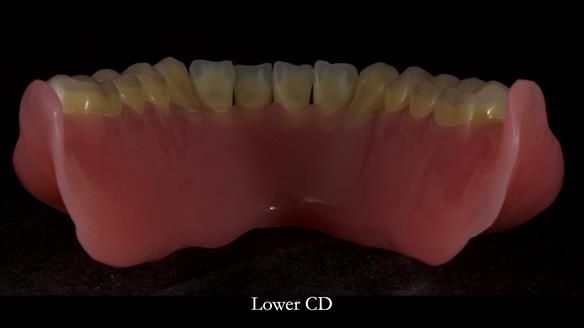

Welcome to Newsletter 83. This month I am sharing Sheila’s case — a very challenging but rewarding complete denture case. Sheila had flat ridges, a small mouth opening, a large tongue and had never been able to wear complete dentures of any kind. Everything was loose and sore. She felt embarrassed and looked older without dentures. She wanted a stable, comfortable result, and she wanted to avoid implants because she has taken bisphosphonates for more than five years.

Because her denture space anatomy was limited, I took two working impressions at the same visit. She had very little space in the lower jaw because of the spread of the tongue and the fact she had never worn a lower denture. This made it difficult to judge exactly where the borders needed to be and how much functional space we truly had.

In Sheila’s case, the Dr Abe shaped impression gave a more stable and comfortable result. Sheila preferred the shape produced by the Abe method, so that is the one we used for the registration rims, the trial denture and the final dentures. But making both impressions was worthwhile. It meant we had every option covered and could choose what worked best for her mouth.

I also want to give a BIG shout out to Rowan, my dental technician. His technical skills are extraordinary, and I could not do this level of work without him. His attention to detail and craftsmanship play a huge part in the success of cases like this.